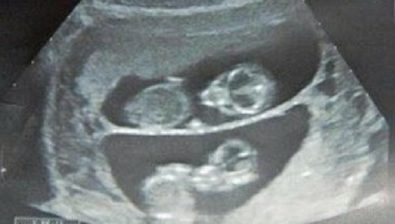

11 Weeks Pregnant: With Twins

Your little swell is likely a full-on baby bump at this point. Twins and multiples have a way of taking up a lot more space!

They also zap your energy and beef up your appetite, too. Pay special attention to how you feel and what your body is telling you.

Those motherly instincts tend to kick in at just the right time, so offer a listening ear to your incredible body.